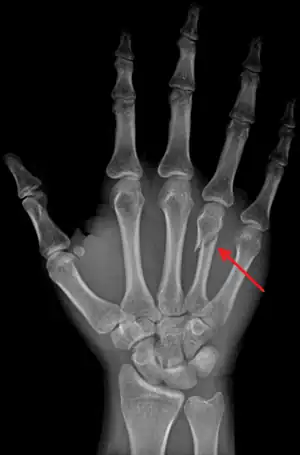

Fractura boxerului, este denumirea comună pentru fractura colului celui de-al cincilea os metacarpian.

![]() Fractura boxerului - aspect radiografic | |